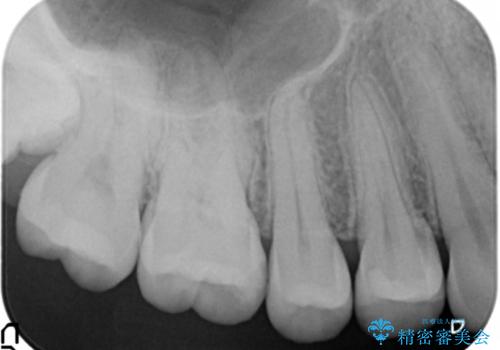

2. 奥歯の虫歯 セラミックインレーで治療の治療中

2.